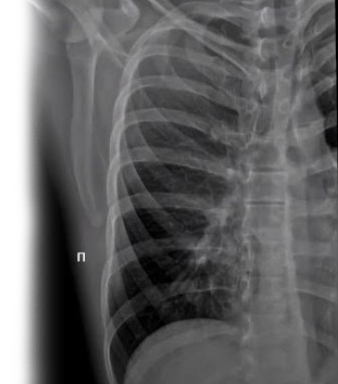

Рентгенография ребер – важный метод прицельного исследования, который позволяет оценить состояние ребер. Диагностическая услуга выполняется в двух проекциях.

Рентген позволяет оценить наличие костно-травматической патологии ребер.